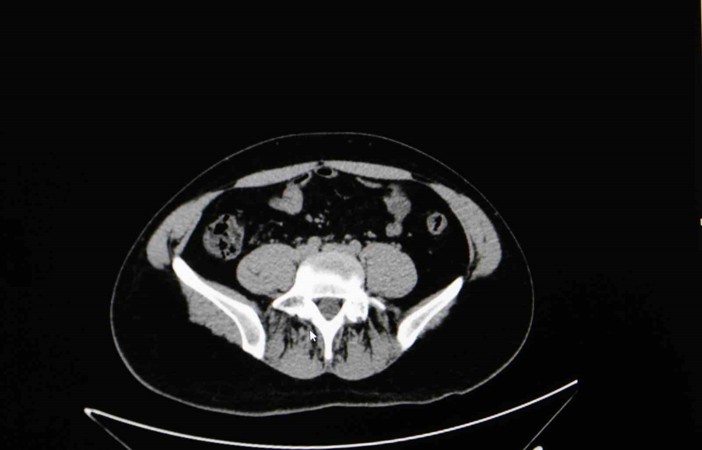

Diyarbakır Dicle Memorial Hastanesi’nde görev yapan Üroloji Uzmanı Op. Dr. Birgi Ercili “Sistit, aslında idrar torbası dediğimiz mesanenin iltihabıdır. Daha çok enfeksiyon sebepleriyle oluşur. Sistin daha çok sebebi idrar yoluna genital bölgeden ulaşan mikroorganizmalardır. Özellikle kadınlarda sistit dediğimiz durum çok fazla görülür. Çünkü kadınlarda üretra dediğimiz idrar yolu, erkeklere göre oldukça kısadır. Vajina ve anüse yakın olduğu için oradan gelen mikroorganizmaların idrar yolu aracılığıyla mesaneye ulaşması daha kolaydır. Kadınların yarısı hayatlarında muhakkak en az bir defa bu hastalığı geçirmektedir” ifadelerine yer verdi.

Sistitin sık görülen belirtilerinden idrar yanması ve az idrar yapma olduğunu ifade eden Ercili, “Sistit geliştiğinde özellikle idrarda yanma, sızı, sık sık ve az idrar yapma, damla damla idrar yapma, kasık ve alt karın bölgesinde ağrı, idrarda kan ve bulanık idrar görülebilir. Bazen de kadınlarda ilişki sonrası ağrı görülebilir. Genital hijyene çok dikkat edilmemesiyle, tuvalet temizliğini arkadan öne doğru yapılmasıyla mikropların idrar yoluna daha hızlı şekilde ulaşabildiğini görmekteyiz. Bunların dışında nemli çamaşırlarla beklemek, sık çamaşır değiştirmemek, az sıvı almak sistite sebep olabilmektedir. İlişki sonrasında da yine idrar yolunda tahriş meydana geldiği için sistit durumlarını görebilmekteyiz” diye konuştu.